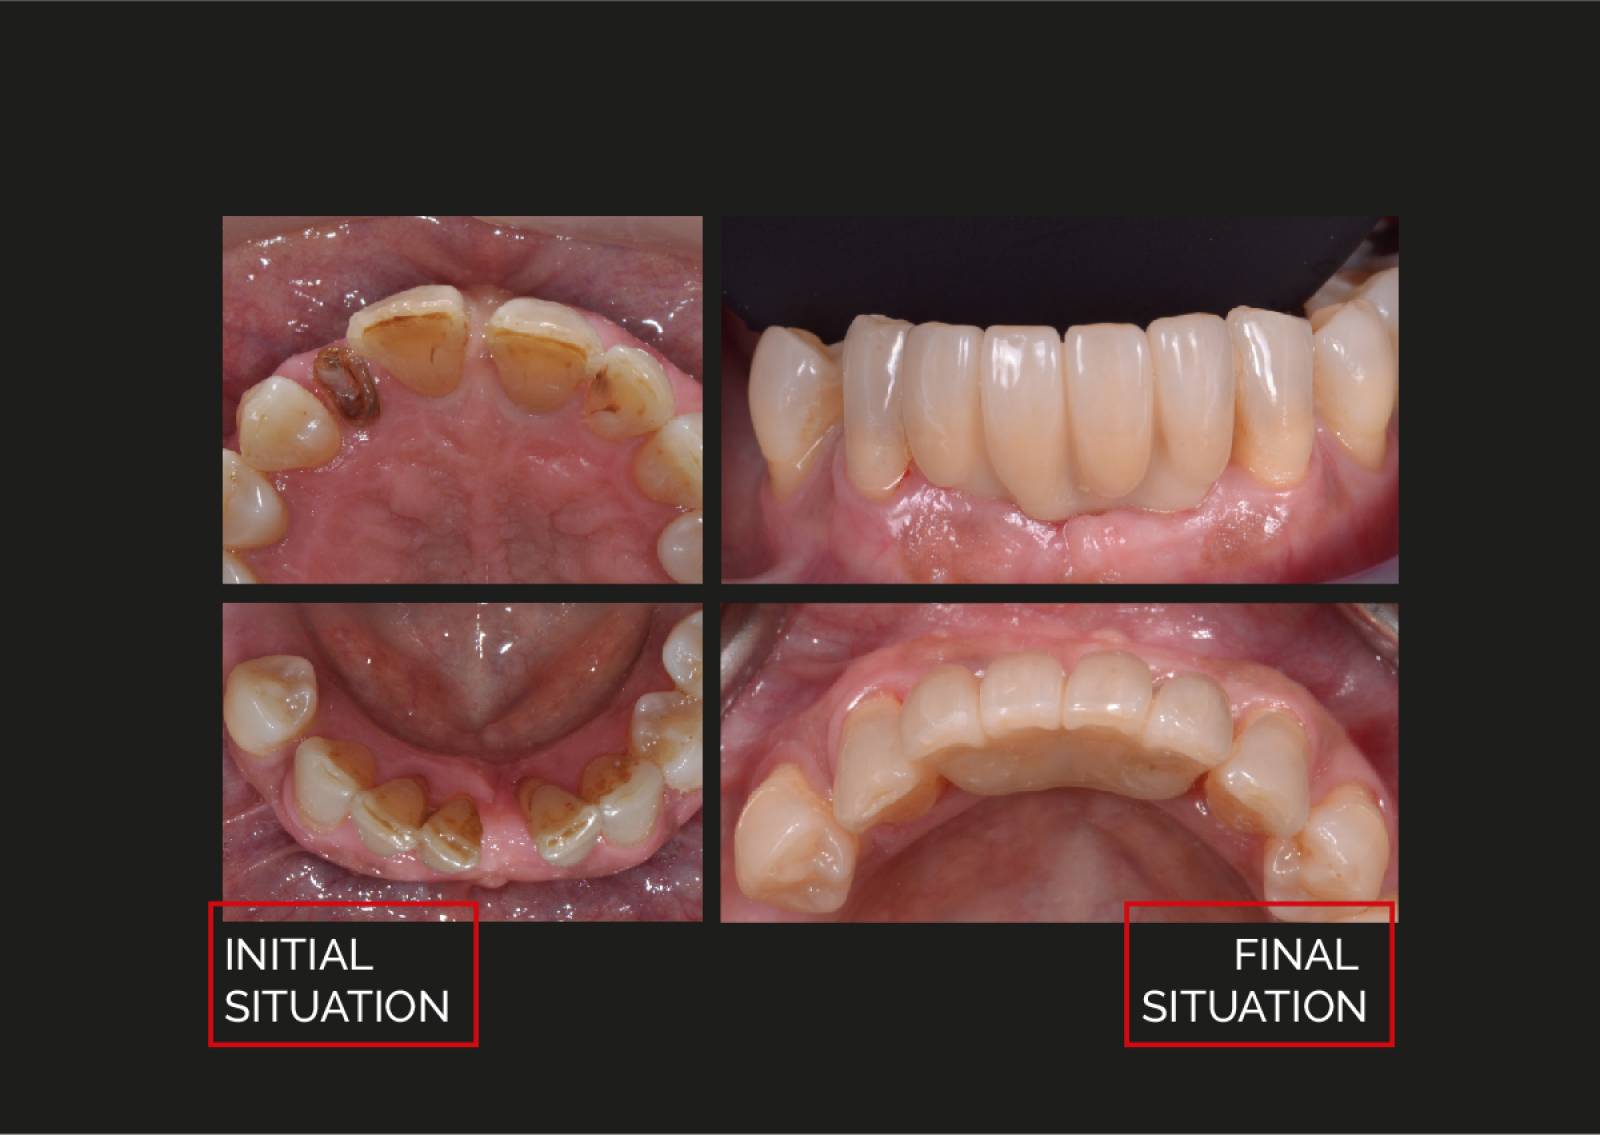

PROSTHETIC

Handling of the matrix® prosthetics.

The precision of matrix® prosthetics.